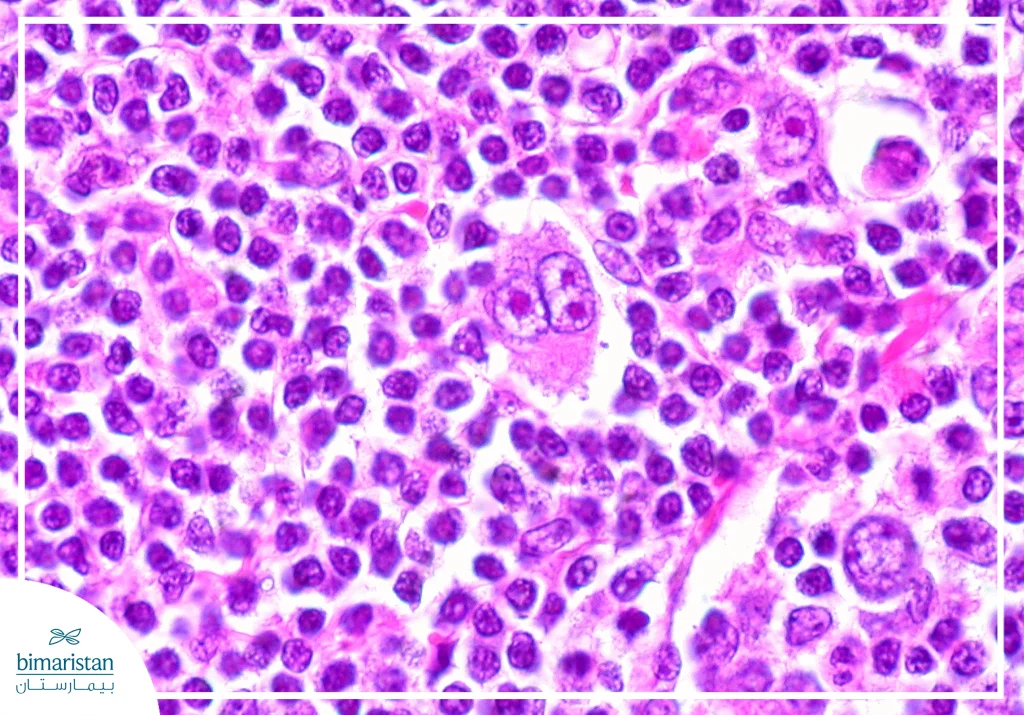

لمفوما هودجكن هو ورم خبيث لمفاوي يتميز بوجود خلايا نوعية مميزة تدعى خلايا ريد – ستيرنبرغ وتتميز بأنها:

- كبيرة الحجم

- متعددة الأنوية

- تعطي مظهر عين البومة

- تنشأ غالباً من خلايا بايئية متحولة

تفرز هذه الخلايا سيتوكينات تجذب خلايا التهابية حولها وهو ما يفسر تضخم العقد اللمفاوية.

عندما نأخذ خزعة من العقدة اللمفاوية ونفحصها تحت المجهر مع فحوص مناعية خاصة، نلاحظ:

- شكل الخلايا الورمية (خصوصاً خلايا ريد–ستيرنبرغ)

- نوع الخلايا الطبيعية المحيطة بها (لمفاويات أو حمضات أو عدلات)

- وجود تليف أو بنية عقدية

- الواسمات المناعية على سطح الخلايا

يكون المشهد النسيجي مختلط بسبب وجود خلايا مناعية عديدة ومتنوعة حول الخلايا الورمية. نرى في الخزعة رشاحة التهابية غنية تضم لمفاويات وحمضات وعدلات وخلايا بلعمية وخلايا ريد–ستيرنبرغ واضحة. يُشاهد أكثر عند كبار السن أو في حال وجود نقص في المناعة، وقد يرتبط أكثر بفيروس EBV مقارنةً بالنوع العقدي المتصلب. يكون الإنذار جيد إلى متوسط حسب المرحلة والانتشار.